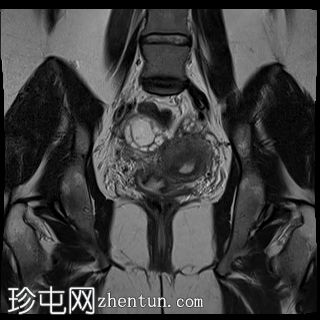

矢状位

T2加权像

双侧卵巢位置接近(卵巢相吻),左侧卵巢内可见一边界清晰的囊性病变,大小约3.1 × 2.7 × 2.9 cm,T1加权像呈高信号,T2加权像可见暗点征及内部暗点征。以上MRI特征符合卵巢子宫内膜异位囊肿的诊断。

右侧卵巢可见一囊肿,大小约为 2.8 × 2.0 × 2.2 cm,T1 加权像呈高信号,囊内可见液-液平面,提示囊内含有不同时期的出血性物质。由于对侧卵巢存在典型的子宫内膜异位囊肿,且该囊肿无强化,影像学表现强烈提示为另一子宫内膜异位囊肿。

子宫大小、轮廓及信号强度均正常,子宫内膜分区结构完整。未见局灶性肌层病变,子宫内膜厚度在正常范围内。

左侧盆腔可见少量游离液体。